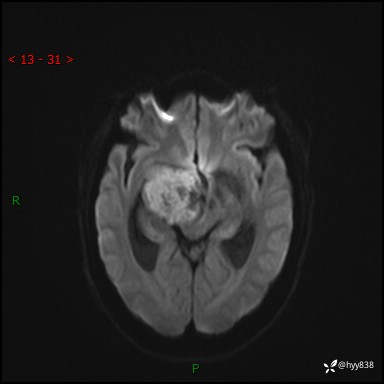

颅脑MRI平扫+增强